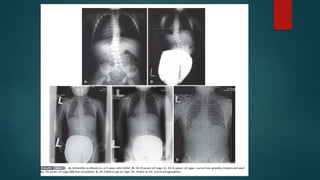

- Infantile scoliosis occurs from birth to 3 years of age

INFANTILE IDIOPATHIC SCOLIOSIS

 Infantile idiopathic scoliosis is a structural, lateral curvature of the spine

occurring in patients younger than age 3 years.

 Most curves in infantile idiopathic scoliosis are self limiting and

spontaneously resolve (70% to 90%); however, some curves may be

 Because of the favourable natural history in 70% to 90% of patients with

infantile idiopathic scoliosis, active treatment often is not required. If the initial

curve is less than 25 degrees and the RAVD is less than 20 degrees, observation

with radiographic follow-up every 6 months is recommended.

 Most resolving curves correct by 3 years of age; however, follow-up should

continue even after resolution because scoliosis may recur in adolescence